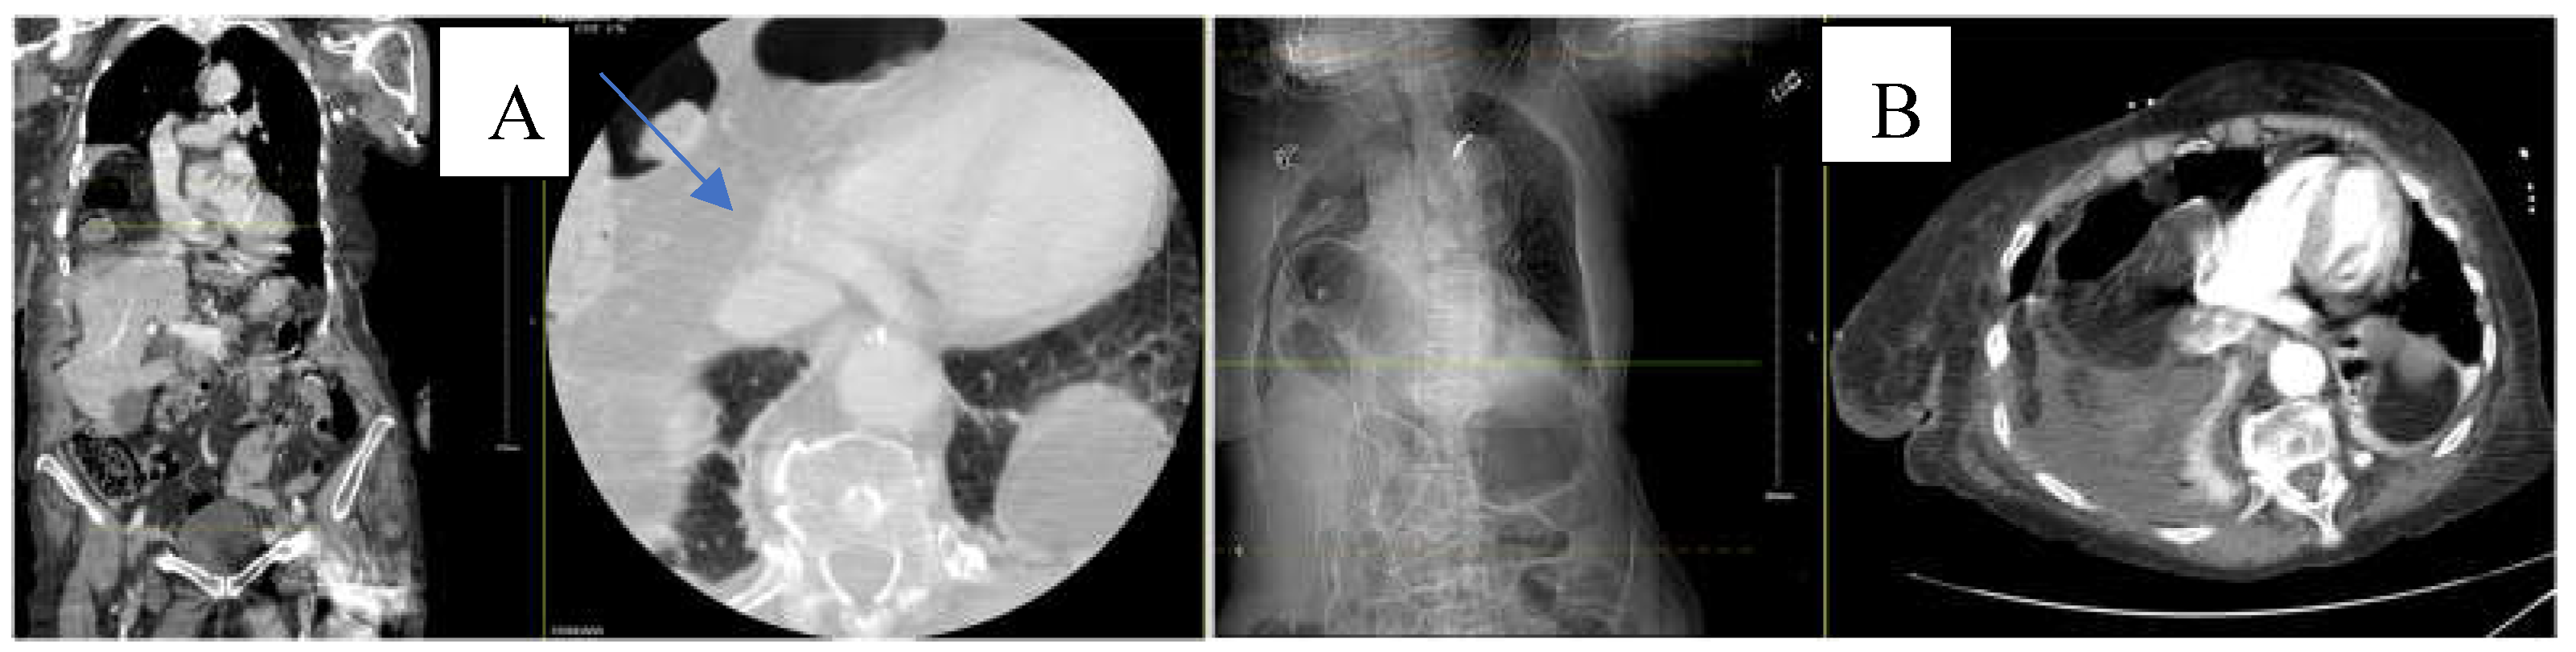

A 28-year-old Asian female with an unknown past medical history was brought by EMS as a pedestrian struck vs jumped in front of a car at a high rate of speed. She was thrown onto her left side. The initial Glasgow Coma Scale (GCS) was 10. On arrival at the ED, the patient was spontaneously moving but mumbling incoherently. Vitals were remarkable for tachycardia, tachypneic, and hypoxia. BP was 136/107 mmHg. The primary survey was notable for deformity of the left forearm and dilated unreactive left pupil. A portable pelvic ultrasound (Figure 3) revealed pelvic fracture. Chest ultrasound showed elevation of the left hemidiaphragm and comminuted diaphyseal fracture of the left humerus with major fragments. CTA of the neck showed C5-C6 with 3 mm posterior subluxation, irregular narrowing of the right vertebral artery extending from C5-7, and nondisplaced coracoid fracture of the left scapula. CT chest with contrast (Figure 4) revealed a distended stomach with air-fluid in the left hemithorax concerning a closed loop obstruction. eFAST was negative for pericardial fluid. CTAP was consistent with CT chest findings including grade 4 splenic injury with contrast extravasation, grade 3 left renal injury with perinephric collection, and multiple pelvic fractures. The patient became hemodynamically unstable and was emergently taken to the operating room (OR) for exploratory laparotomy. The stomach was successfully reduced into the abdominal cavity from the thorax and on exploration, the diaphragm was noted to have a 6 cm defect, which was repaired with 2-0 ethibond in interrupted fashion with a total of 8 stitches. The patient also underwent splenectomy due to pulsatile red blood extravasation. On the same admission, neurosurgery performed anterior cervical discectomy and fusion and open reduction internal fixation (ORIF) of open humerus fracture and pelvic fracture. Two days after admission, she was taken back to the OR for repair of liver capsular laceration and facial closure. The patient was discharged on postoperative day 47 in stable condition. ISS was 41.

Figure 4. CT of the chest with contrast showing distended stomach with air and fluid in the left hemithorax (orange arrow), diaphragmatic defect, and grade IV splenic injury parenchymal laceration greater than 3 cm.